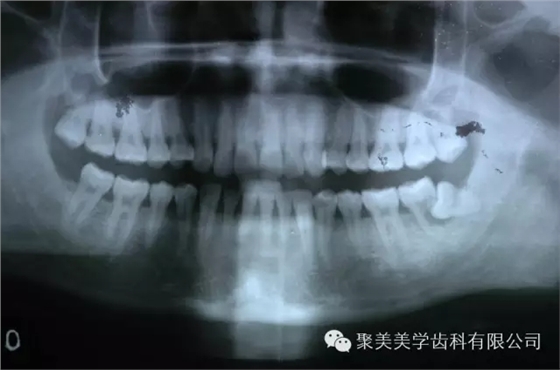

阻生牙把前面的牙齒頂壞了,兩個(gè)牙齒都需要拔除!

被阻生牙頂壞的相鄰牙無法治療,只能拔除了,非常可惜!